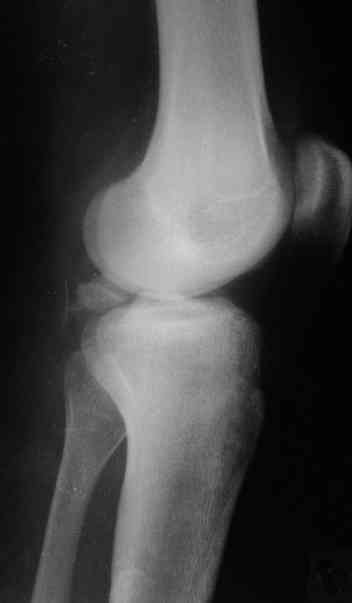

В 3 из 4 случаев мы применили винт, проведенный ретроградно по аналогии с фиксацией заднего края большеберцовой кости при переломах в

области голеностопного сустава. В прищепке рентгенограммы одного из наших пациентов до операции и спустя полгода. Остальные 3 наблюдения

описаны в статье "Изолированный отрывной перелом большеберцовой кости в месте прикрепления задней крестообразной связки // Вестник

травматологии и ортопедии им. Приорова. - 2001. - №1. – С. 38-40. Если есть интерес, могу прислать копию. Ваш случай, безуловно, отличается величиной костного фрагмента, его локализацией, характером и степенью смещения. Но думаю, принцип лечения может быть общим.